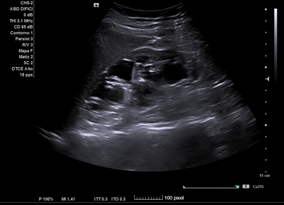

En ecografía clínica desde el centro de salud, se objetiva gran dilatación del sistema excretor del riñón derecho, con adelgazamiento de la cortical (hidronefrosis grado III-IV). No se aprecia litiasis u otra causa obstructiva a nivel renoureteral ni vesical. Riñón derecho conserva tamaño normal. Riñón izquierdo de tamaño y ecoestructura normales, sin dilatación piélica. Vejiga bien replecionada sin alteraciones en su pared.